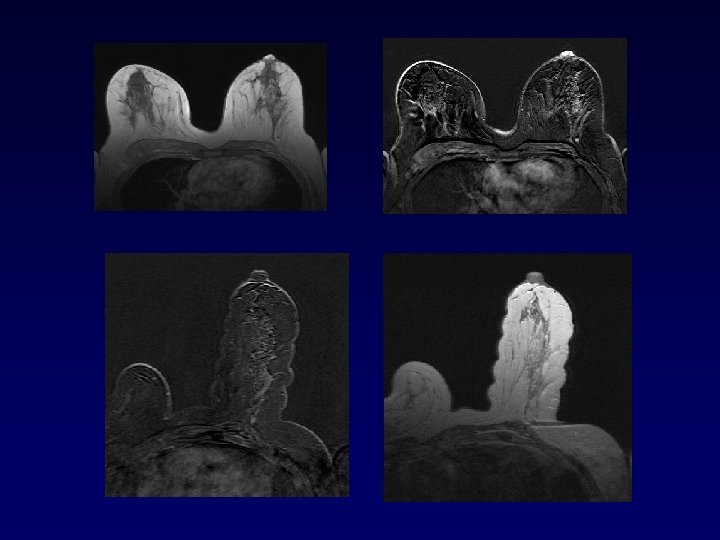

IRM et CCIS : la fin du consensus ? • Etude Lancet 2007 (C Kuhl) – 5960 patientes – Comparaison Mammographie/IRM – 167 diagnostic de CCIS – 89 CCIS de haut grade – Sen pour CCIS haut grade : • IRM = 98% • Mammographie = 52%

Performance de l’IRM pour le diagnostic de CCIS • Peu de résultats – Non indication de l’IRM (mammographie / microcalcifications) – IRM plus performante pour diagnostic de CCIS de haut grade que de bas grade – Potentiel dans le bilan d’extension • Les CCIS représente un taux important des cancers biopsiées sous IRM (> taux des cancers découverts par IRM) (64 CCIS pour 74 K invasif dans la série multicentrique européenne – Cancer 2006)

Angiogénèse dans CCIS haut grade